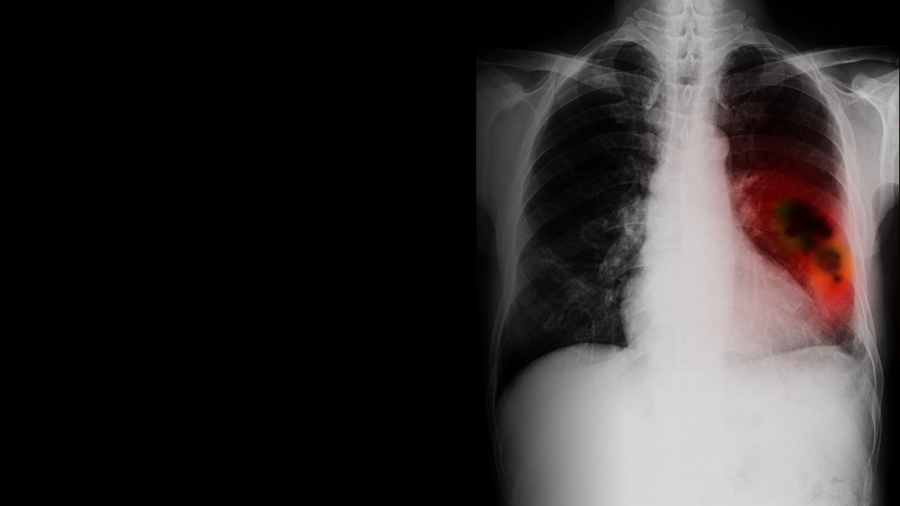

The committee did not recommend even a limited and narrowly targeted screening program despite saying it would reduce deaths from lung cancer.